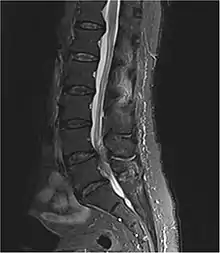

MRI of an abscess causing cauda equina syndrome

Diagnosis is first suspected clinically based on history and physical exam and usually confirmed by an MRI scan or CT scan, depending on availability.[4] Bladder scanning and loss of catheter sensation can also be used to evaluate bladder dysfunction in suspected cases of cauda equina syndrome and can aid diagnosis before MRI scanning. Early surgery in acute onset of severe cases has been reported to be important.[4]